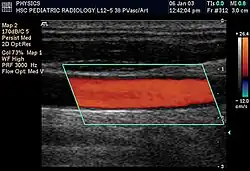

A ultrassonografia (BR) ou ecografia (PT) é um método diagnóstico muito recorrente na medicina moderna que utiliza o eco gerado através de ondas ultrassônicas de alta frequência para visualizar, em tempo real, as estruturas internas do organismo. Por meio de uma ultrassonografia com doppler, o médico é capaz de ver o fluxo sangüíneo nos principais vasos.

Em aplicações médicas de ultrassom, a onda detectada é frequentemente uma reflexão de tecido em movimento, como hemácias no sangue. A diferença entre as frequências contém informações sobre a velocidade do objeto. Essas informações podem ser usadas para criar mapas de fluxo sanguíneo.

Power Doppler é um método de processar o sinal que se baseia na amplitude de todos os sinais Doppler, independente da direção do movimento (ou seja, da direção do fluxo). Isso melhora a sensibilidade ao movimento, ao custo da informação da direção do fluxo. Maior sensibilidade permite a detecção e interpretação de fluxos sanguíneos muito sutis e lentos.